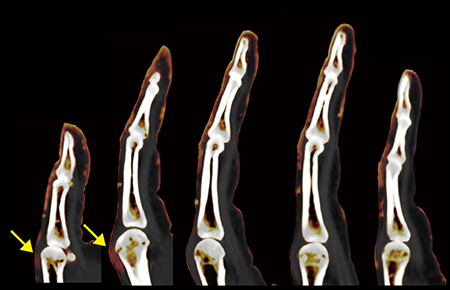

症例2は40歳代,女性。乾癬歴15年で,右手関節痛の症状が出たことからDECTを施行した。尺側手根伸筋に腱鞘炎が明瞭に描出されている(図3↓)。DECTでは,5指それぞれに対し中手骨頭から末節骨まで観察可能な矢状断像を作成できる(図4)。

また,本症例では,第1指と第2指の中手骨頭背側に伸筋腱周囲炎を認め(図4↓),さらに冠状断像,横断像を併せて読影することで,MCP関節やPIP関節の滑膜炎を指摘できた(図5 ←)。DECTでは,アーチファクトの少ない複数断面の画像を作成でき,放射線科医としても自信を持って評価することが可能である。

図4 症例2:全指に対する各矢状断の再構成